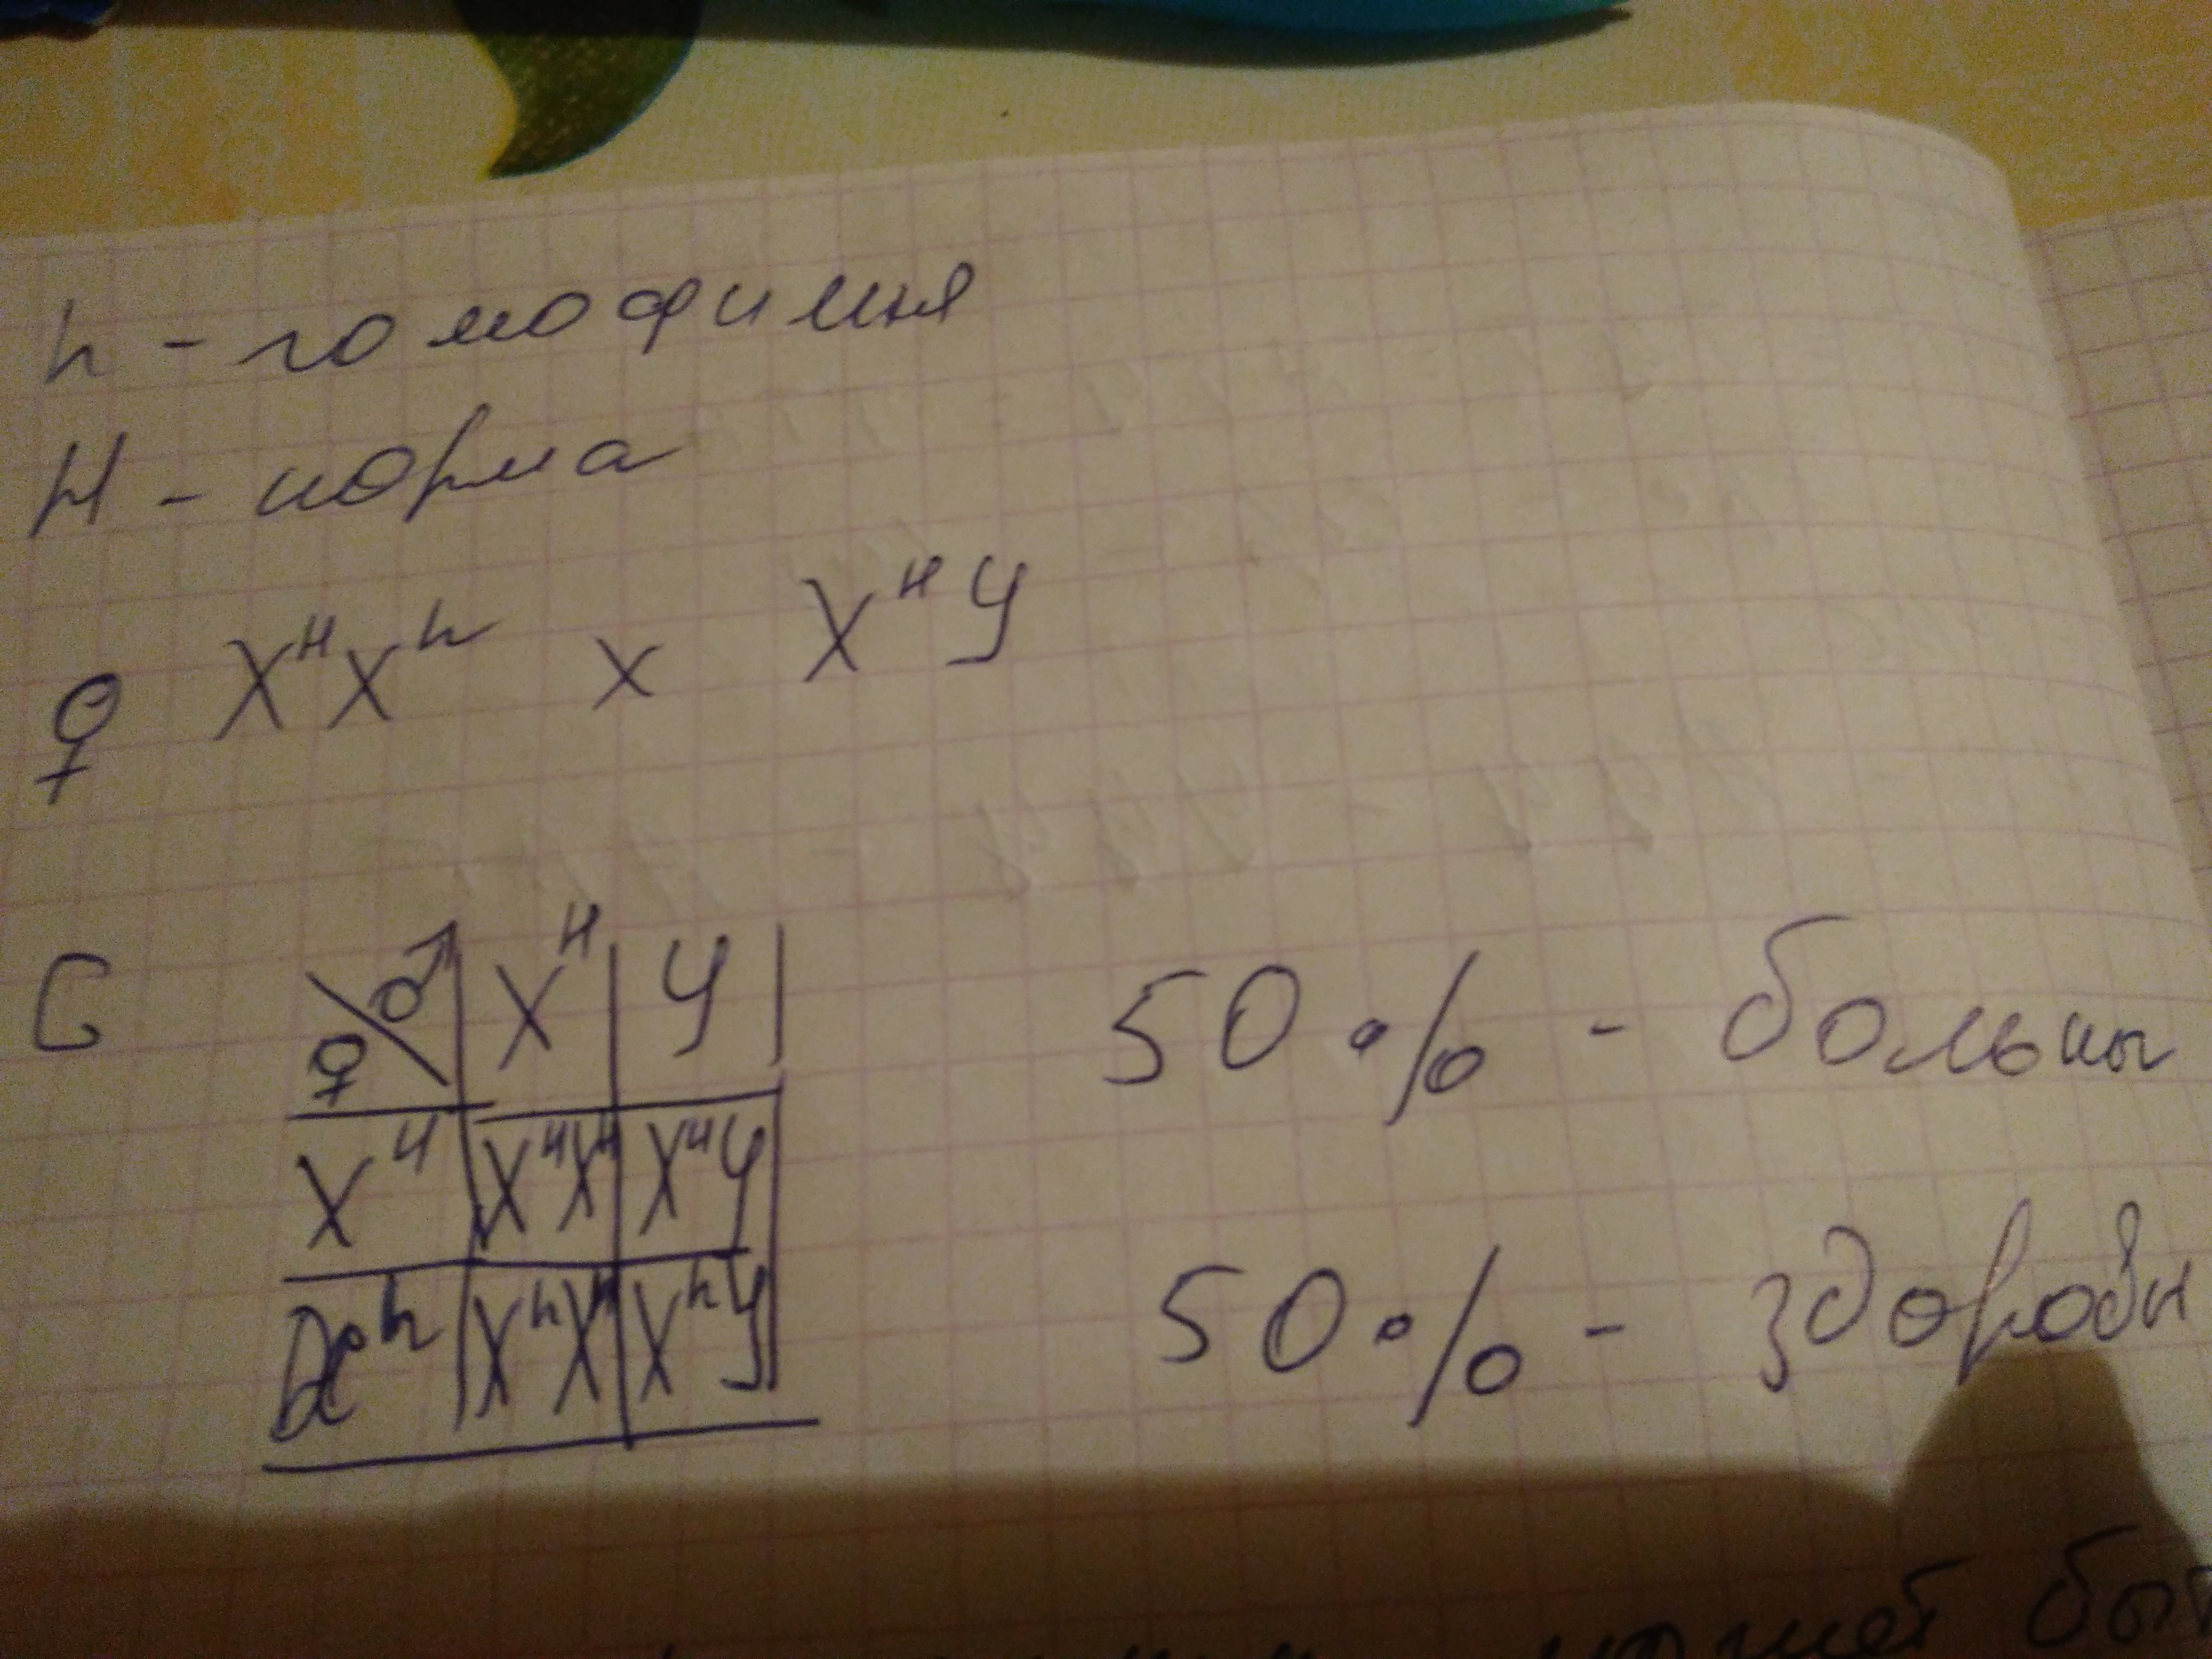

Генетика гемофилии: рецессивные гены и их проявления